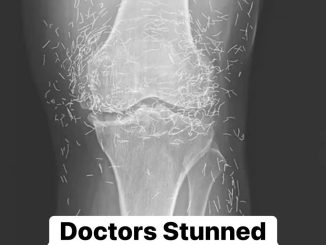

X-Ray Leaves Doctors Astonished After Examining Woman With Joint Pain

An Unexpected Find Doctors in South Korea were stunned when a routine knee X-ray of a 65-year-old woman revealed hundreds of tiny gold needles lodged […]